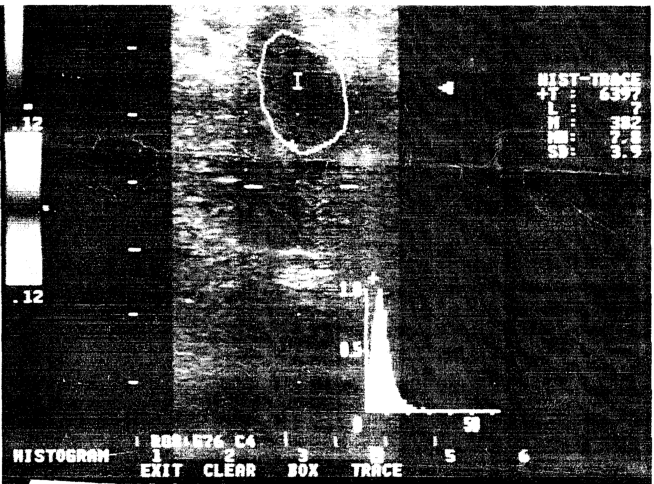

Способ осуществляют следующим образом (см.чертеж). Ультразвуковое исследование проводят по стандартной методике (4) в горизонтальном и вертикальном положении пациента. Проводят поперечное, затем продольное сканирование. Больной находится в положении лежа на спине со слегка ротированными наружу ногами. Датчик устанавливают в области паховой складки параллельно ей. Получают поперечный срез общей бедренной артерии и вены. Бедренную вену находят медиальнее одноименной артерии. Оценивают диаметр просвета, толщину стенок вены, проводят пробу с компрессией датчиком. Перемещают датчик в дистальном направлении, исследуют область сафено-бедренного соустья, поверхностной и глубокой бедренных вен. Развернув датчик, получают продольный срез вен. При продольном сканировании оценивают контур стенок, просвет сосуда, работу клапанов. Клапаны визуализируются во время вдоха, при проксимальной компрессии передней брюшной стенки, при пробе Вальсальвы и перестают быть видимыми во время выдоха и при дистальном сдавливании мышц бедра. Типичные признаки обструкции глубоких вен наиболее отчетливо выражены в паховой, менее – в подколенной областях и не определяются в задних большеберцовых венах. Определяют участок вены с тромбом, выделяют с помощью трассировки в области дефекта наполнения и определяют показатель MEAN с помощью функции гистограмм (5).

Применение функции гистограммы позволяет проводить оценку преобразования тромба на этапе его эхонегативной картины. Использование функции гистограмм осуществляет вывод эхосигнала на произвольном участке и показывает распределение интенсивности на ограниченном трассировкой месте локализации тромба. По расчетной формуле определяют средний уровень интенсивности на участке дефекта кровенаполнения

l- уровень интенсивности, соответствующий чаще всего встречающей составляющей интенсивности на заданном участке MEAN и при ее значении менее 1,2 определяют норму, при ее значении от 1,5 до 10 определяют первую степень активности, при ее значении от 10 до 15 вторую степень активности, а при ее значении 15 и более третью степень активности процесса тромбообразования.

При использовании функции гистограммы в первые сутки показатель MEAN=1,5, что указывает на неорганизованность тромба, что соответствует первой степени активности. На пятые сутки после назначения антикоагулянтной терапии, адекватной в данном случае, MEAN=14,3, что говорит о консолидации тромба, плотной фиксации к стенке сосуда и, как следствие, о снижении риска тромбоэмболии легочной артерии, и этот показатель соответствует второй степени активности тромбообразования.